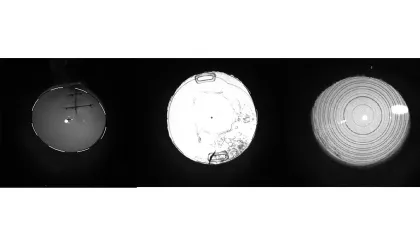

Die in Abbildung 1 gezeigten Auswertungen werden zusammen mit den Kunden besprochen. Bei der Bewertung der Messungen gehen wir in der Beratung schrittweise vor. In den Scheimpflugbildern kann die Transparenz der Hornhaut beurteilt werden, mögliche Hornhautnarben oder -trübungen leuchten im Schnittbild stärker auf. Die Augenlinse wird ebenfalls durchleuchtet und lässt einen Rückschluss auf den Transparenzgrad zu. Hier hilft auch die Retroillumination enorm (Abb. 2). Somit kann sich der Optometrist ein Bild über die Abbildungsfähigkeit des Auges machen. Unseren Kunden erklären wir die Aufnahmen – für viele ist dadurch ihr täglicher Seheindruck besser verständlich.

Abb. 2: (Links) Alle im Strahlengang befindlichen „Ablenkungen“ sind dank der Retroillumination gut erkennbar. Eine vertikale Hornhautperforation wurde mit Einzelknüpfnähten versorgt. An den Einstichstellen des Nahtmaterials sieht man die Zugkräfte des Fadens. (Mitte) Zu erkennen sind eine Intraokularlinse und die Ansatzbereiche der Haptiken. Die Kasulorhexis ist nur wenige Millimeter groß und im inferioren Bereich sind Elschnig-Perlen des Nachstars zu erkennen. (Rechts) Die konzentrischen Ringe einer Multifokal-Intraokularlinse heben sich deutlich im Retroilluminationsbild ab. Damit lassen sich Zentrierung und Lage der Intraokularlinse im Vergleich zum Pupillenzentrum beurteilen.